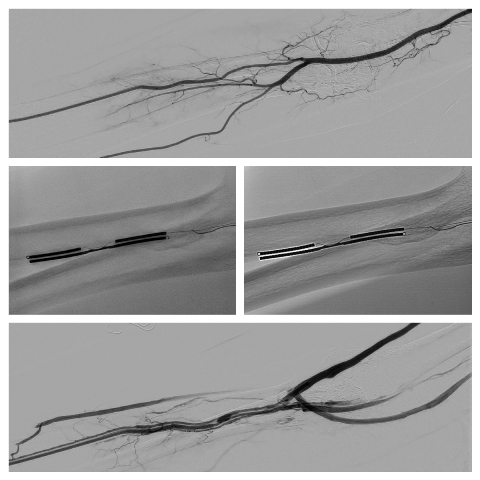

La tecnica si avvale di un sistema costituito da due cateteri angiografici (sottili strutture filiformi) che vengono introdotti per via percutanea (rispettivamente, in un vaso venoso ed in un vaso arterioso particolarmente vicini ed opportunamente appaiati), permettendo la creazione di una comunicazione tra i due vasi (Fistola Artero Venosa) attraverso l’applicazione di energia a radiofrequenza focalizzata tra i due cateteri da opportuno generatore esterno. La FAV viene dunque allestita senza bisturi, evitando così al paziente lo stress emotivo e fisico e le cicatrici di un intervento chirurgico tradizionale. Ma la nuova tecnica, eseguita finora in pochi casi al mondo, offre anche altri vantaggi: permette, infatti, una maggiore sopravvivenza della stessa FAV e quindi un risparmio delle riserve vascolari del paziente grazie al minor tasso di complicanze stenotiche, frequente causa di malfunzionamento dell’accesso vascolare. Tutto ciò si traduce, inoltre, in un risparmio economico non indifferente per il Servizio Sanitario, dal momento che la più frequente causa di ricovero per i pazienti emodializzati consiste proprio nel malfunzionamento della Fistola Artero Venosa.